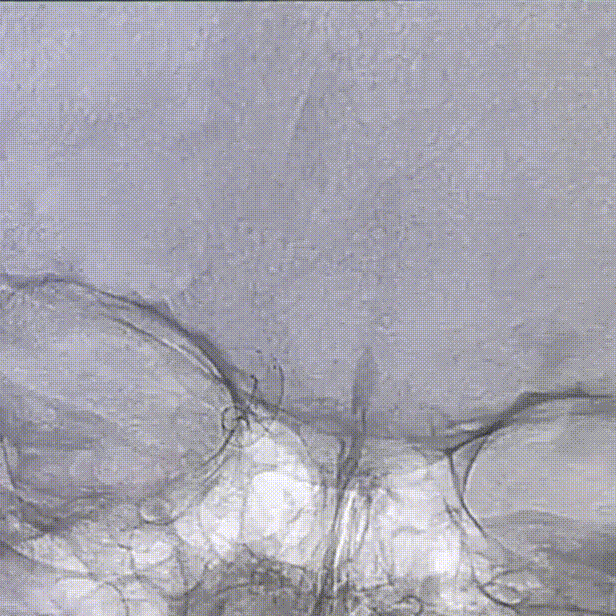

3D-DSA检查

术前诊断

1、右侧颈内动脉床突段动脉;

2、右侧颈内动脉眼动脉段多发动脉瘤;